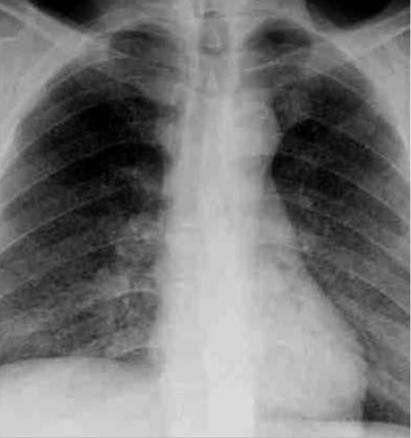

Tuberculose pulmonaire

Radiographie thoracique. Miliaire tuberculeuse.